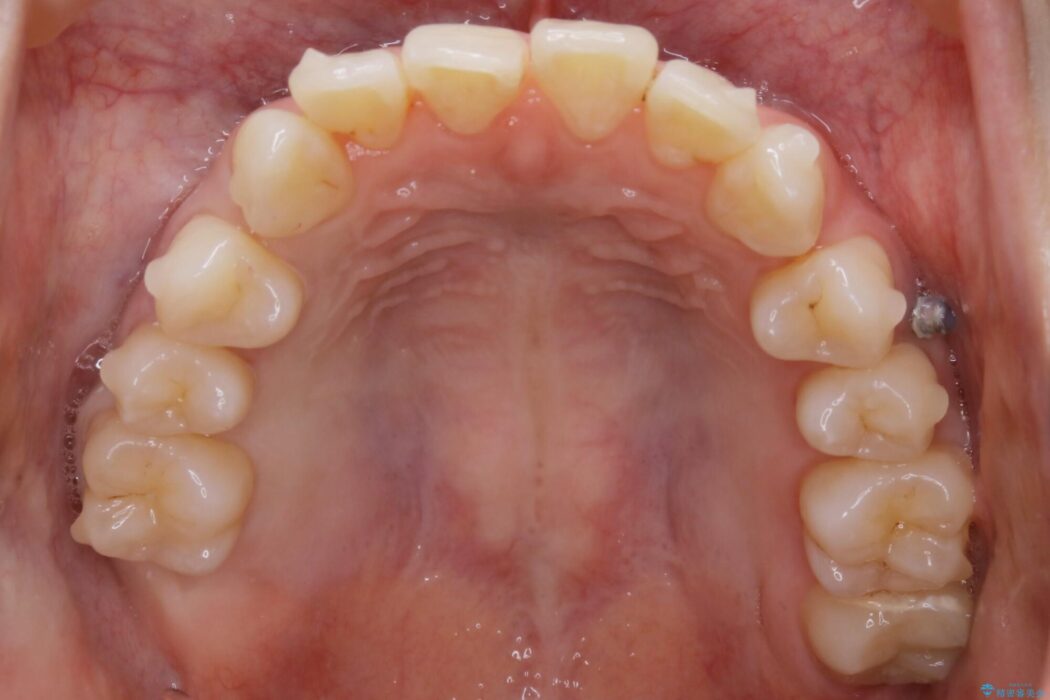

【20代女性】ブライダルに向けた矯正できれいなスマイルラインへ

笑った時に見える歯並びをきれいにしたいとの主訴で来院されました。

ガタつきの度合いから抜歯は不要と判断しましたので、マイクロインプラントを用いて歯全体を遠心移動させていくことでねじれや噛み合わせのズレを改善していく計画を立てました。